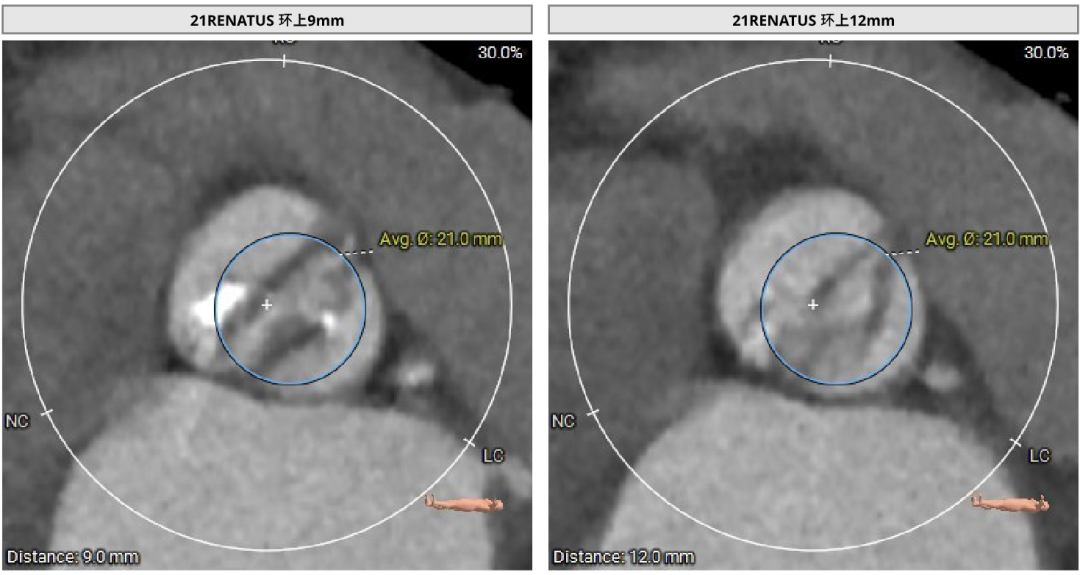

使用Supra annulus画圆法评估21# RENATUS瓣膜植入情况:

患者Type1 二叶瓣,右无融合,融合嵴钙化,钙化主要分布瓣叶缘和融合嵴处,无冠窦底钙化向下延伸至流出道4mm处。Annulus面积398mm²,LVOT面积400mm²,SOV 27.6-30.9mm,STJ高度21.3mm,内径29-32.7mm,瓣环角度62°,升主动脉扩张,左冠高度14.9mm,左冠瓣叶长度15.7mm,右冠高度15.8mm,右冠瓣叶长度9.2mm,模拟植入21#瓣膜VTC LCA 2.4mm,右侧髂内分叉处可见钙化,右侧髂外动脉最细为6.1mm,左侧髂外动脉最细为6.1mm,外周入路尚可。

左冠高度14.9mm,左冠瓣叶长度15.7mm,右冠高度15.8mm,右冠瓣叶长度9.2mm,模拟植入21#瓣膜VTC LCA 2.4mm